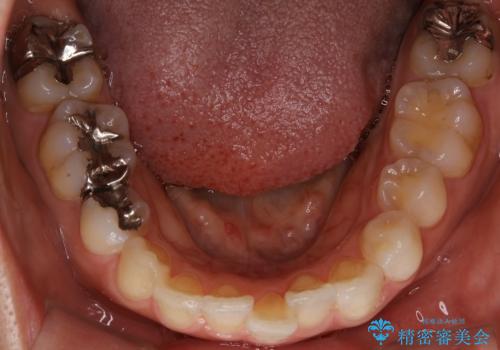

前歯のガタつきを改善 抜歯矯正後の後戻り

- 抜歯矯正後の後戻りで前歯ガタつきが主訴で来院された患者様です。

後戻り矯正や非抜歯矯正はインビザラインをご案内する事が多いですが、自己管理の煩わしさから、目立たないワイヤー装置にて矯正治療を行うこととしました。

後戻りの程度としては軽度なので、治療期間としては短く終えることが出来ました。